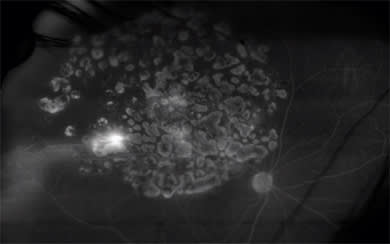

Using this device, our practice has examined 264 eyes in 143 diabetes patients. The images were graded for macular edema (focal, 31%; diffuse, 26%), neovascularization (posterior, 30%; anterior, 19%), nonperfusion (macular, 11%; peripheral, 54%) and late peripheral vessel leakage (41%) (Figure 3).

Figure 3. Peripheral vascular abnormalities are detected using widefield angiography in diabetic retinopathy.